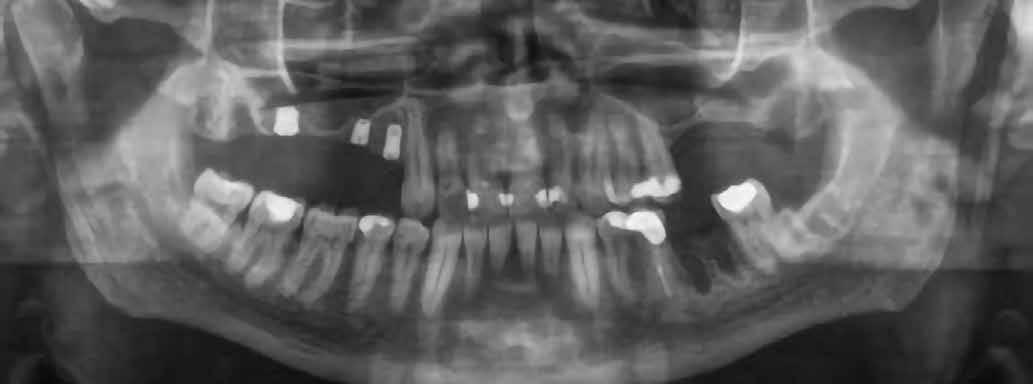

1. ábra: Megfelelő szájhigiénia – panorámaröntgen. 2. ábra: A 2.5, 2.6 és 2.7-nek megfelelő terület a röntgenfelvételen.

és jelentős mobilitással rendelkezett. A radiológiai vizsgálat után egyértelműen látszódott, hogy a fogon még nem végeztek gyökérkezelést. A 2.6-os és 2.7-es fogaknak megfelelő területen az arcüreg kiterjedése jelentős volt, vertikális csontmennyiség szignifikánsan csökkent (1. és 2. ábra).

A végső röntgenfelvételen láthatjuk az osszeointegrálódott implantátumokat, valamint a stabil kresztális gerincet az azonnal behelyezett, a rövid és a ferde, a tuberben elhorgonyzott implantátum körül (12. ábra).